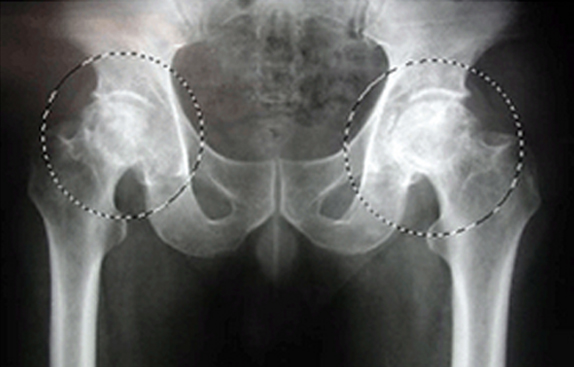

고관절에 발생한 무혈성 대퇴 골두 괴사

우측 고관절의 인공 고관절 전치환술 후 상태